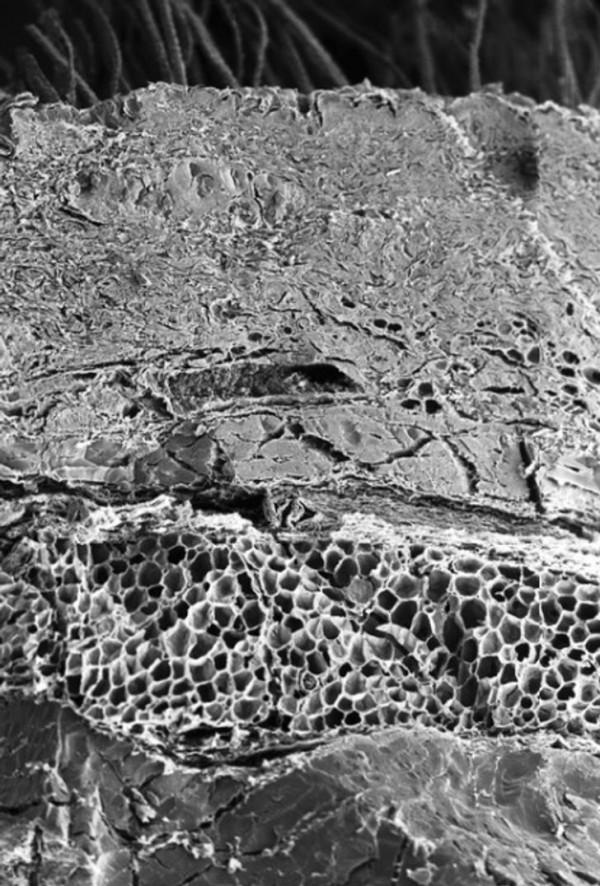

骨頭